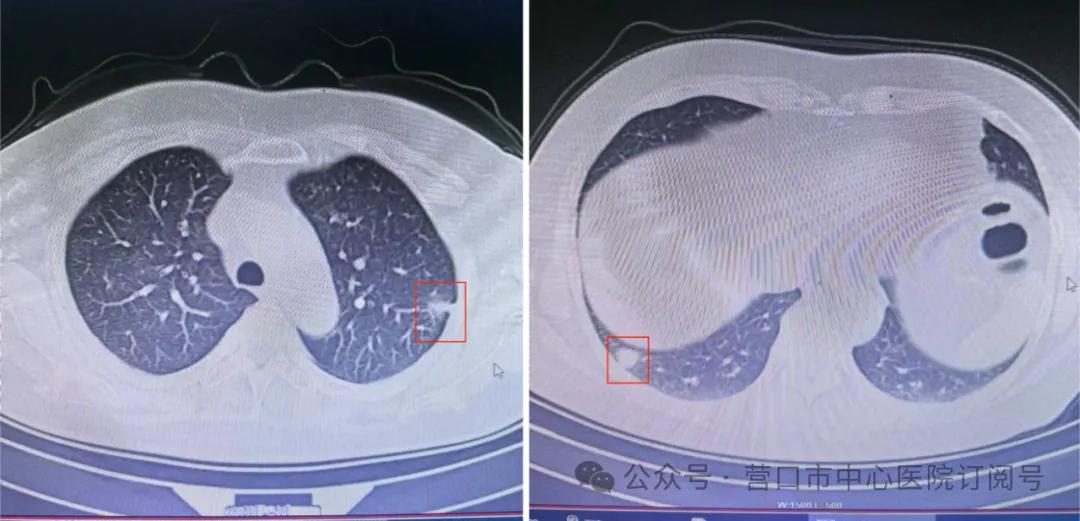

家住市区的曾女士今年61岁,两个月前,因持续咳嗽到医院就诊,CT检查发现其两肺多发磨玻璃结节,其中最大的有1.5厘米大小并且伴有实性成分。近两个月的跟踪复查双肺结节均有所增大,曾女士寝食难安,深感担忧。为尽早明确诊断,近日,曾女士在家人的陪伴下来到营口市中心医院胸外科就诊。曾女士之前就听说过市中心医院副院长黄波教授是胸外科微创领域的专家,并且擅长双肺结节的同期治疗,于是通过门诊接触到了黄波副院长。

黄波副院长耐心地查看了患者的所有相关资料,发现曾女士的左肺上叶和右肺下叶都有混合密度的磨玻璃结节,均考虑早期肺癌。黄波副院长带领胸外科解纲主任团队,经过充分术前讨论和评估,在介入血管外科、病理科、麻醉科、手术室的密切配合下,为患者实施“单孔胸腔镜左肺上叶解剖性部分切除术+同期单孔胸腔镜右肺下叶解剖性部分切除术+系统性纵隔淋巴结清扫术”。手术过程顺利,冰冻病理和术后病理均为早期肺癌,与术前判断完全一致。手术历时2小时30分钟,手术切口仅3厘米,双侧肺癌同期切除成功。